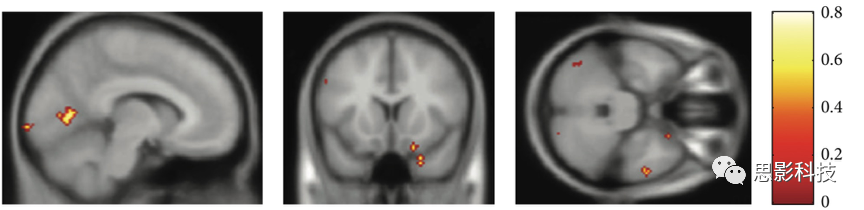

3.dMRI指標(biāo)。dMRI(彌散磁共振)數(shù)據(jù)經(jīng)頭動(dòng)渦流校正、張量擬合等預(yù)處理步驟后,可得到FA、MD、AD、RD等指標(biāo)。以上指標(biāo)可以在體素水平計(jì)算。

圖示.彌散影像指標(biāo)。